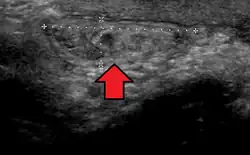

Ultrassom mostrando hérnia inguinal

No diagnóstico de hérnias abdominais, a imagem é o principal meio de detectar hérnias diafragmáticas internas e outras hérnias não palpáveis ou não suspeitas. A tomografia computadorizada com múltiplos detectores (TCMD) pode mostrar com precisão o local anatômico do saco de hérnia, o conteúdo do saco e quaisquer complicações. A TCMD também oferece detalhes claros da parede abdominal, permitindo que as hérnias sejam identificadas com precisão.[9]

De longe, as hérnias mais comuns (até 75% de todas as hérnias abdominais) são as chamadas hérnias inguinais. As hérnias inguinais são ainda divididas na hérnia inguinal indireta mais comum (2/3, representada aqui), na qual o canal inguinal é inserido através de uma fraqueza congênita em sua entrada (o anel inguinal interno) e o tipo de hérnia inguinal direta (1/3), onde o conteúdo da hérnia passa por um ponto fraco na parede traseira do canal inguinal. As hérnias inguinais são o tipo mais comum de hérnia em homens e mulheres. Em alguns casos selecionados, eles podem exigir cirurgia. Há casos especiais em que a hérnia pode conter hérnia direta e indireta simultaneamente hérnia pantalonariana, ou, embora muito rara, pode conter hérnias indiretas simultâneas.[15]